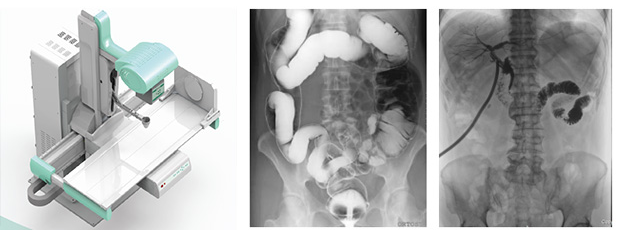

多功能DR大大提高了普通放射設(shè)備準(zhǔn)確診斷的能力,為臨床創(chuàng)造了價(jià)值,它可以進(jìn)行全身各部位的拍片、透視和點(diǎn)片攝影。接下來小編給大家介紹一下這三種模式的區(qū)別。

拍片攝影是利用X線穿過人體被檢查部位并感光在膠片上形成影像而進(jìn)行診斷的方法,它有膠片可供長時(shí)間觀看分析,便于診斷分析及會(huì)診讀片、資料存儲(chǔ)。另外,由于曝光時(shí)間很短,人體受到的輻射比透視小得多。但是當(dāng)某處有疑點(diǎn)時(shí)無法轉(zhuǎn)動(dòng)體位從不同角度觀察,無法看全貌。

透視是用X線穿過人體被檢查部位在熒光屏上顯示的影像而進(jìn)行診斷的方法,連續(xù)出射線(攝影),在檢查時(shí)可以轉(zhuǎn)動(dòng)病人的身體,從各種不同的位置和角度來觀察病變的狀況,也可以觀察器官的運(yùn)動(dòng)功能,能夠立即得到檢查結(jié)果,進(jìn)行介入性的操作等。但是因?yàn)橥敢晻?huì)持續(xù)輸出射線,病人接受的輻射劑量較大,并且透視對(duì)細(xì)微病變和厚實(shí)部位觀察不太清楚,不能留下長久性的記錄。

點(diǎn)片攝影是在透視的條件下,對(duì)病變部位進(jìn)行可視化觀察,待發(fā)現(xiàn)疑似病變部位的時(shí)候進(jìn)行瞬間點(diǎn)片,從而能夠準(zhǔn)確獲取病變部位的高清影像用于臨床診斷,從而在一定程度上降低漏診誤診率。病人不動(dòng),通過選擇鍵由透視直接切換攝影的曝光過程。在透視過程中,保存一幅靜止的圖像。常用于消化道、膽系造影下的攝影等。它既可以觀察運(yùn)動(dòng)器官的運(yùn)動(dòng)功能,又能在有感興趣的圖像時(shí),對(duì)膠片曝光保留感興趣的圖像,便于進(jìn)一步診斷。